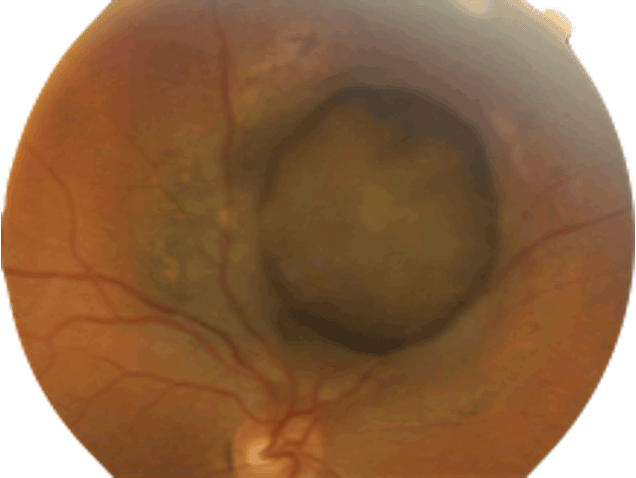

Mélanome choroïdien Diagnostic du mélanome choroïdien Il s'agit de la tumeur intraoculaire primitive la plus fréquente de l'adulte. Le mélanome uvéal peut toucher la choroïde (site le plus fréquent que nous décrirons ici), le corps ciliaire ou l'iris. Son incidence annuelle est d'environ 500-600 nouveaux cas par an en France. L'âge médian au diagnostic est de 62 ans mais il peut survenir à tout âge. Il touche généralement les sujets caucasiens, avec un surrisque parmi les personnes ayant les yeux bleus, pour des raisons non encore élucidées. Le diagnostic est clinique, ce qui est une singularité en oncologie, car l'obtention d'une preuve histologique par biopsie invasive exposerait à un risque de dissémination orbitaire. Il repose sur l'examen du fond d'œil et l'échographie oculaire. On observe une lésion choroïdienne en relief (Figures 1 et 2), de morphologie en dôme ou en champignon (Figure 3). La lésion est souvent pigmentée mais peut également être achrome (Figures 4 et 5), ce qui doit alors faire suspecter une métastase choroïdienne, avec réalisation d'un bilan d'extension complet, à la recherche d'une néoplasie primaire ayant métastasé à l'œil. Un décollement de rétine exsudatif peut être présent (Figure 6). Une hémorragie intravitréenne peut s'associer et masquer la tumeur. Ces deux présentations impliquent de devoir réaliser systématiquement une échographie oculaire en cas de décollement de rétine exsudatif sans déhiscence retrouvée, ou en cas d'hémorragie intravitréenne. En effet, une éventuelle chirurgie intraoculaire par vitrectomie sur un mélanome uvéal méconnu peut entraîner une dissémination tumorale.

Figure 3 Échographie oculaire montrant un mélanome choroïdien en dôme (A) et en champignon (B).